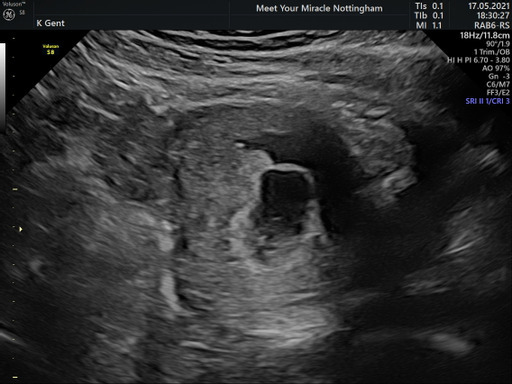

MrsGxx · 18/05/2021 15:21

Hello ladies - New here. First of all congratulations to everybody💕

I had an early dating scan yesterday which put me around 7 weeks and a day or 2 (ish) she said and gave me an EDD of 2nd January, although to me I get around 26th December?